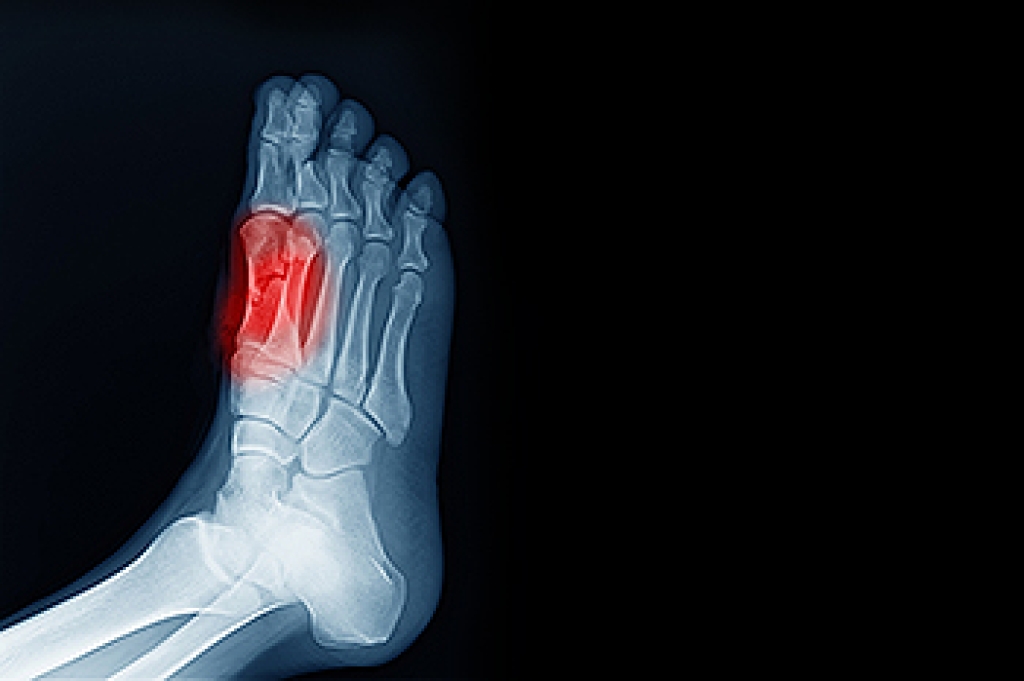

Morton's neuroma is a painful foot condition that commonly affects the areas between the second and third or third and fourth toe, although other areas of the foot are also susceptible. Morton’s neuroma is caused by an inflamed nerve in the foot that is being squeezed and aggravated by surrounding bones.